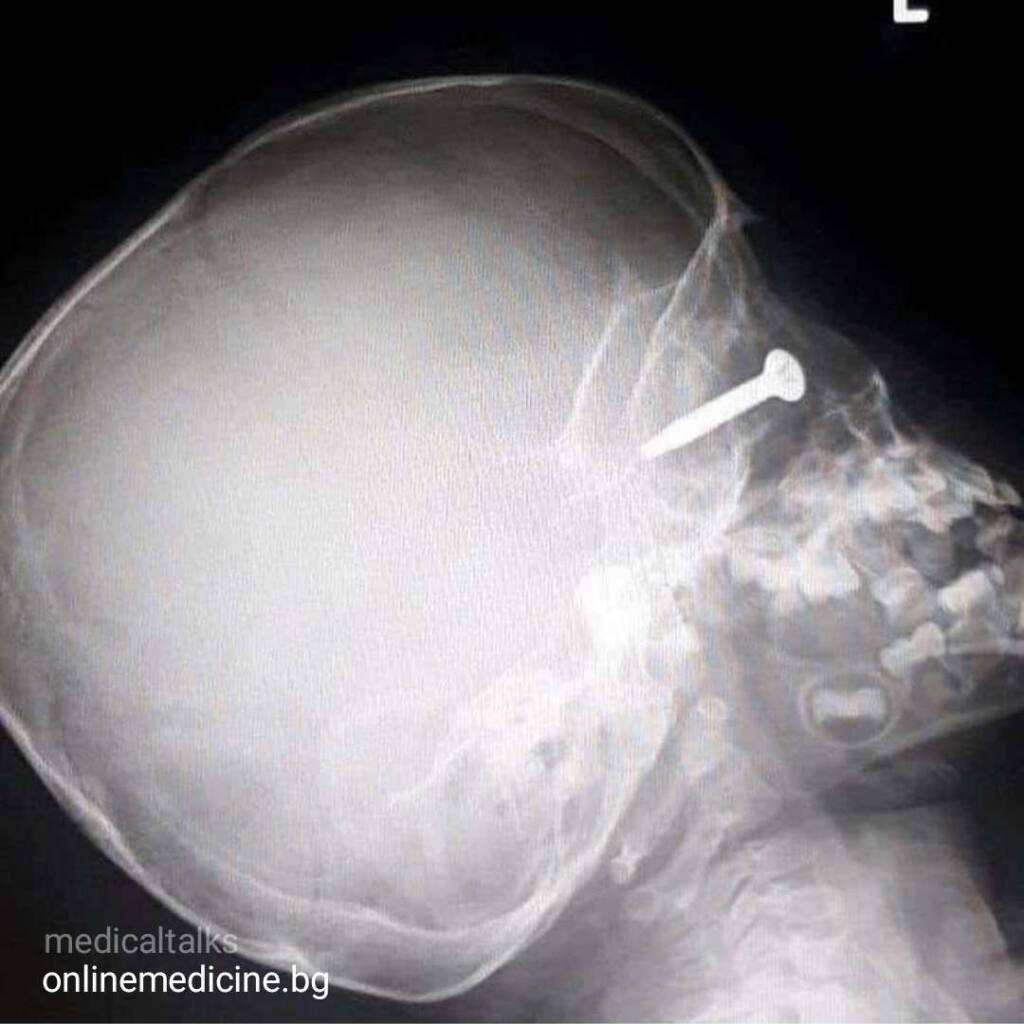

Клиничен казус 11: Чуждо тяло в окото

Чуждо тяло в около, нещастен инцидент сполетява 3-годишно момче. Чуждо тяло прониква в лявото око на детето, след като от косачка за трева рикошира винт! Бащата на детето косил трева, но за страданието на острието на косачката удари метален винт […]